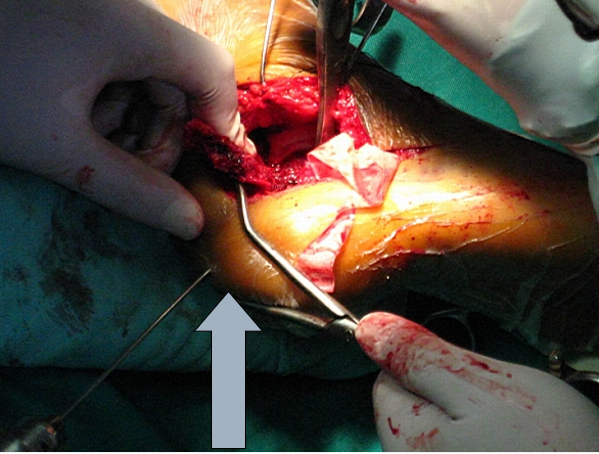

骨刀将跟骨外侧壁翻开,同时跟骨内翻即可清晰显露距下关节和跟骨后关节面

技巧四、如何恢复跟骨的长度以及高度这样撬拨恐怕只能恢复跟骨的高度,因为没有纵向的牵引。

我们的方法是:大巾钳位于跟骨结节上方,向下后牵引跟腱

技巧六、如何恢复跟骨的宽度对于Sander‘s分型Ⅳ型骨折,外侧壁膨出,跟骨增粗明显。这时可以用简单的暴力给予复位-----锤击

它带来的额外收益是:跟骨体部的骨质缺损间隙消失,而不必植骨。

在放跟骨板之前,用击锤锤击跟骨外侧壁,恢复跟骨宽度。此时应保持克氏针在维持正常的复位位置

它带来的额外收益是,跟骨体部的骨质缺损间隙消失,而不必植骨。